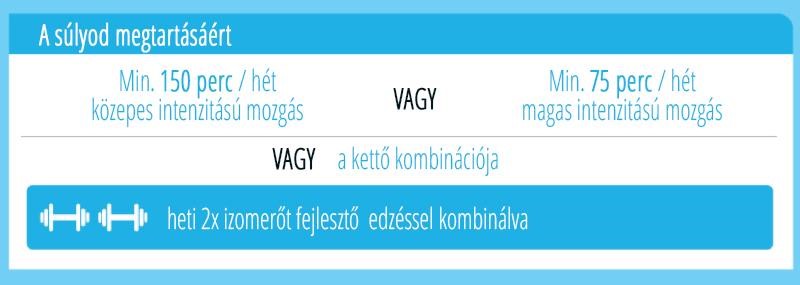

Az edukáció olyan fontos kérdéseket érint, mint: mi számít meddőségnek, mikor érdemes szakemberhez fordulni, hogyan hat az életkor a termékenységre, illetve milyen kockázatot jelentenek a szexuális úton terjedő fertőzések. Az iránymutatás külön kitér a legfontosabb kockázati tényezőkre, mint a dohányzás, a túlzott alkoholfogyasztás, az elhízás vagy éppen az alultápláltság, melyek mind kedvezőtlenül hathatnak a reproduktív egészségre. Ezzel szemben a kiegyensúlyozott, tápanyagokban gazdag étrend, a rendszeres testmozgás, valamint a dohányzás elhagyása bizonyítottan hozzájárulhat a termékenység megőrzéséhez és a későbbi problémák megelőzéséhez.